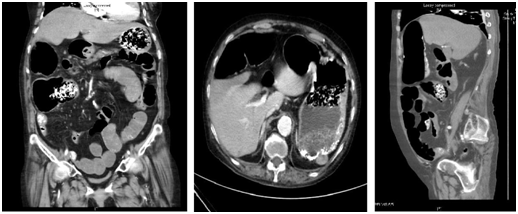

A computed tomography scan of Abdomen and Pelvis (CTAP) revealed distended small and large bowel loops, more so the colon, most significantly at the ileo-cecal junction. Pneumatosis of the cecum and terminal ileum was detected. There was mixed density pattern material in the stomach, terminal-ileum and cecal junction, suggestive of food material, which is not surprising in this case as this was an emergency CT scan. No pneumoperitoneum, free fluid or collection was detected. There was herniation of the small bowel into the mesentery. The celiac artery and superior mesenteric artery were patent, no occlusion or thrombosis was seen. There was also no cut off point suggestive of intestinal obstruction due to adhesion of tumor recurrence (Figure 2).

Figure 2 CT abdomen-Pelvis with contrast showing distended bowel and presence of bezoar.

The impression at that point of time was ischemic bowel secondary to intestinal obstruction due to small bowel herniation versus non-occlusive mesenteric ischemia. The patient then underwent an emergency exploratory laparotomy, completion colectomy with end ileostomy and on table endoscopy immediately. Intra-operatively, there was finding of a gangrenous cecum and ascending bowel with ischemic transverse colon (Figure 3), omentum adhered to pelvis and left iliac fossa due to adhesions from previous surgery. There was also internal herniation of small bowel via mesenteric window. In general, the small bowels were healthy, other than mildly dilated and having moderate adhesions of small bowel. Ischemic bowels with ulcerations were seen in the colon specimen. An on-table colonoscopy of rectal stump, which was done to determine the viability of the large bowel, showed healthy mucosa. Retrospectively, the histology of the excised specimen revealed mucosal necrosis, which was consistent with ischemia, as well as viable muscular is propria at bowel resection margins.

Figure 3CT abdomen-Pelvis with contrast showing distended bowel and presence of bezoar.